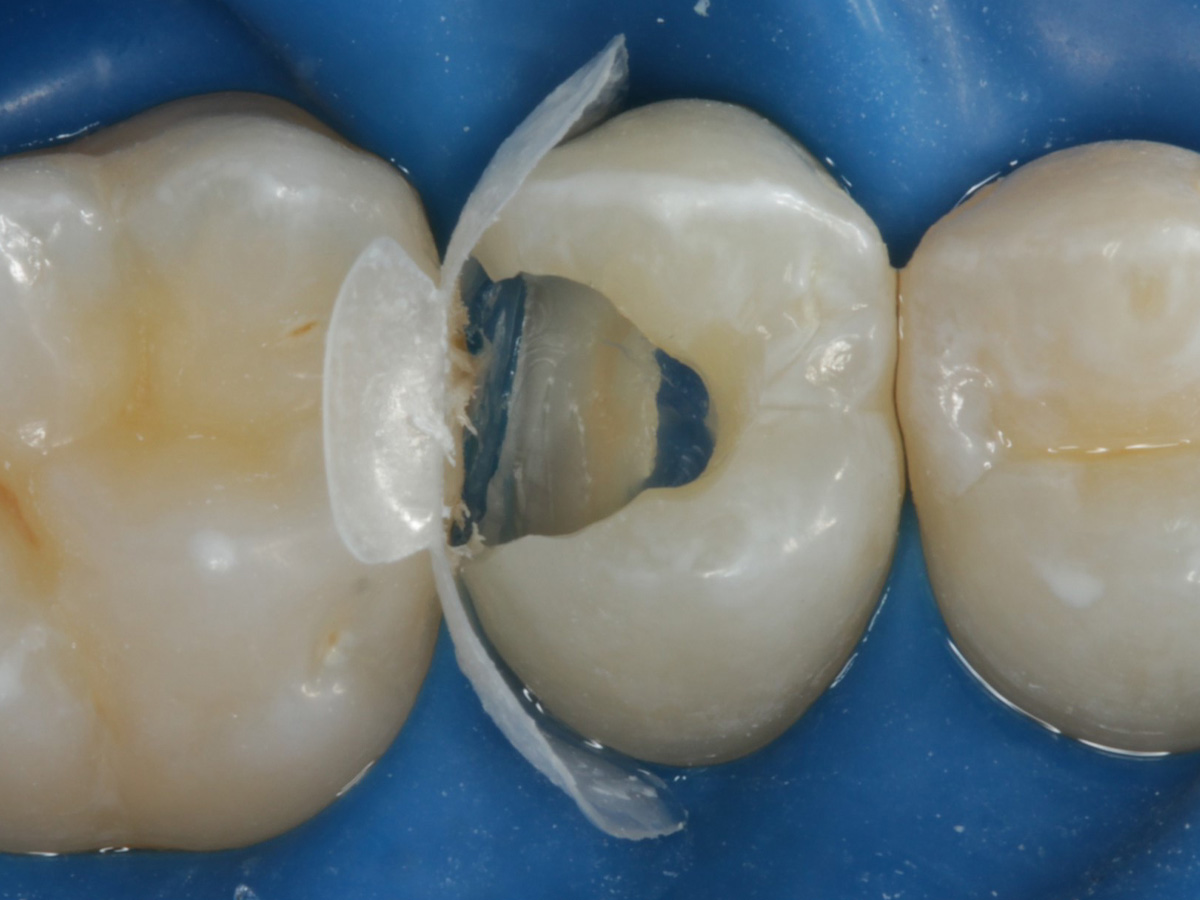

Abbildung 2

Intakte Kaufläche